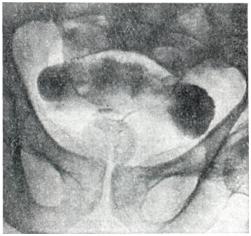

Рис. 5.

Симптом «берета» (лакунарная цистограмма).

Применяют экскреторную урографию, цистографию и уретроцистографию; наиболее рациональна лакунарная уретроцистограмма по Кнайзе и Шоберу (рис. 4). Кислород, введенный по катетеру в количестве 150—200 мл, растягивает мочевой пузырь в виде купола. Введенное вслед за кислородом жидкое контрастное вещество (20% раствор сергозина в количестве 20 мл) располагается в области дна мочевого пузыря, выявляя внутрипузырный рост аденомы предстательной железы. Этим методом определяют ряд типичных рентгенологических симптомов: «берета» (рис. 5), удлинения мочеиспускательного канала (рис. 6), «клинка сабли» (рис. 7), приподнятого дна.